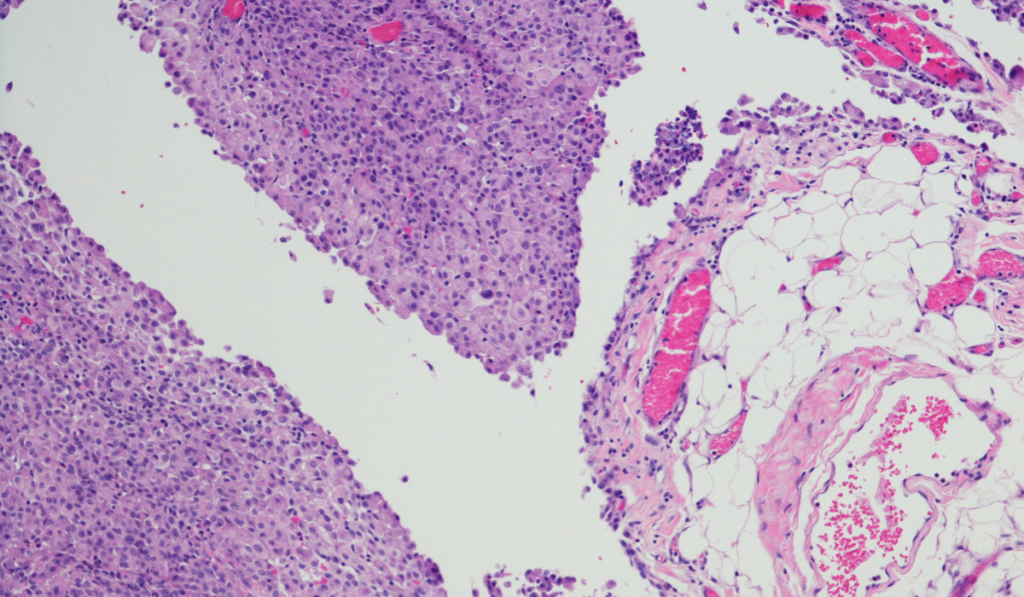

Just like real-world tumors, mesothelioma cell lines aren't all exactly alike. They can originate from different locations in the body where mesothelioma typically forms, such as the pleura (lungs) or the peritoneum (abdomen). Furthermore, these cell lines can represent the different histological subtypes of mesothelioma, including epithelioid, sarcomatoid, or biphasic cells. This diversity is incredibly useful, as it allows scientists to study the various forms of the disease and understand why treatments might work better for some patients than others.